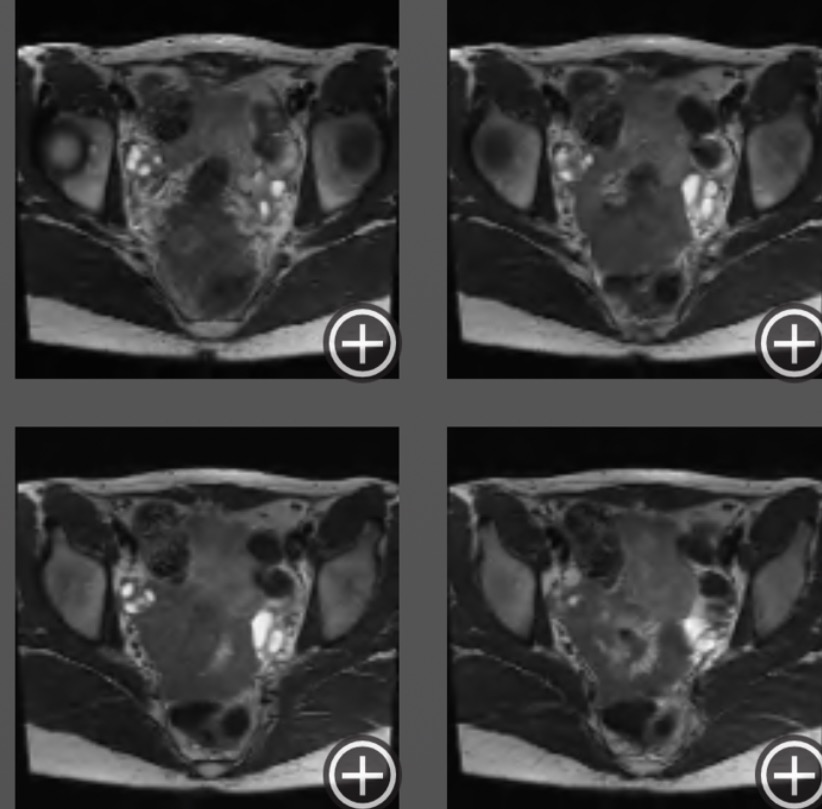

After years of unexplained pain, I finally have an answer — deep infiltrating endometriosis. It means endometrial tissue has grown deep into multiple organs: my uterus, colon, bowels, and urethra.